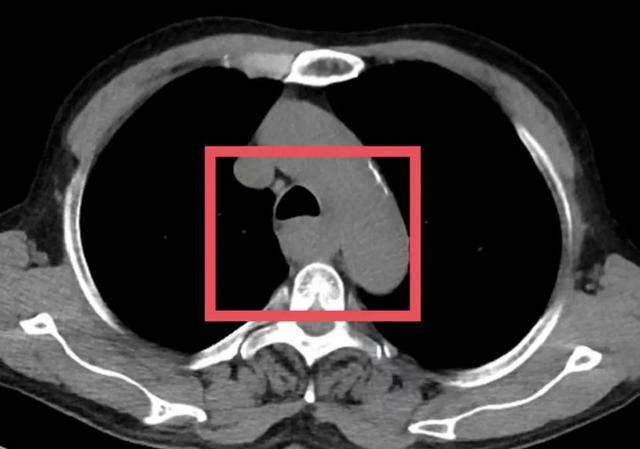

▲患者术前影像学检查

面对肿瘤,不少患者会直观地认为“早点动手术”是最好的选择。但事实上,对于像苏先生这样的局部晚期患者而言,贸然手术可能风险更大,远期疗效也难以保障。

为了争取更大的根治机会,胸外科朱震主任医师为苏先生量身定制定了一套治疗方案——“免疫联合化疗”的新辅助治疗方案,先“软化”肿瘤、减少侵犯,再择期手术。治疗期间,苏先生接受了PD-1单抗与铂类+紫杉醇联合化疗。随着治疗推进,患者主诉症状显著缓解。2025年7月复查CT提示病灶缩小、边界清晰、与周围结构粘连减少,手术时机成熟。